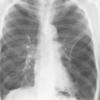

COPD

Date: 06/06/2004

Views: 14537